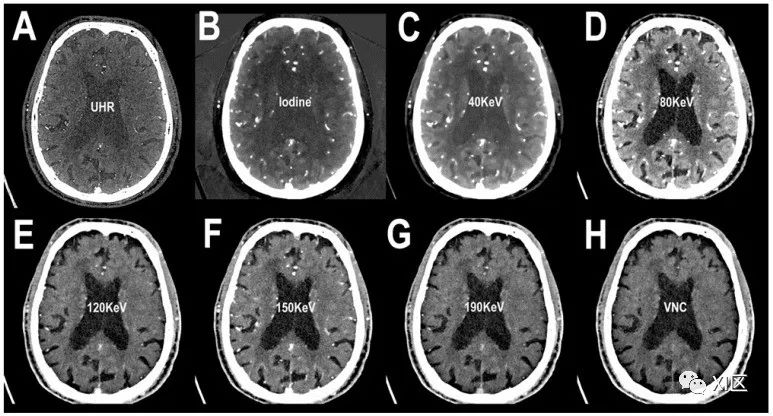

头部PCCT血管造影:单色成像。图中显示的是静脉注射造影剂后在动脉期进行的脑扫描的轴向切片图像。在(A)中,可以看到超高分辨率(矩阵1024×1024;层厚/增量0.2/0.1mm;体素100 μm;卷积核Bv60;辐射剂量与使用同类第三代双源CT进行的头部血管造影相当)。由于获取的图像富含整个keV光谱,因此在(B)中可以看到碘光谱的相同切片。从(C-G)中可以看到同一切片在不同keV设置下的图像,从40 keV到190 keV。虽然可以像(B)中那样用碘谱重建图像,但也可以重建并减去碘谱(即由碘化造影剂决定的对比度增强),形成虚拟平扫图像(VNC)(H)。通过一次PCCT采集,可以获得多个多参数信息。